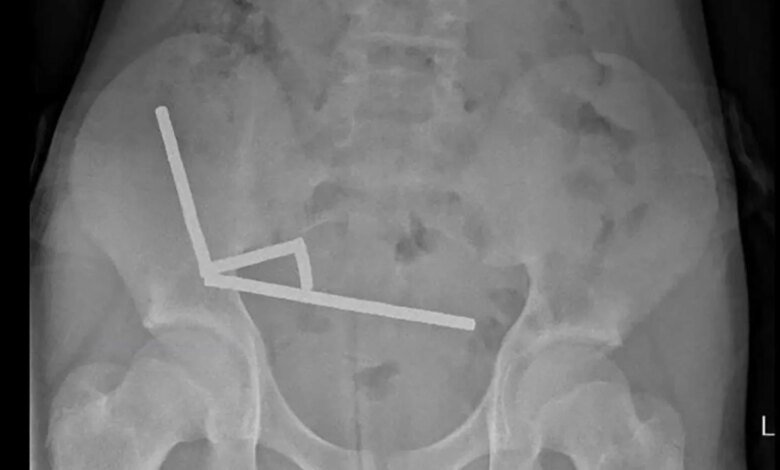

Researchers said an X-ray was taken and showed “four linear chains of magnets” linked together, composed of what the boy indicated was “approximately 80–100 5x2mm high-power (neodymium) magnets” that he allegedly purchased from online retailer Temu.

Photos published in the study showed the retrieval process, and indicated that the magnets “appeared to be in separate parts of bowel” but were “adhered together due to magnetic forces.”